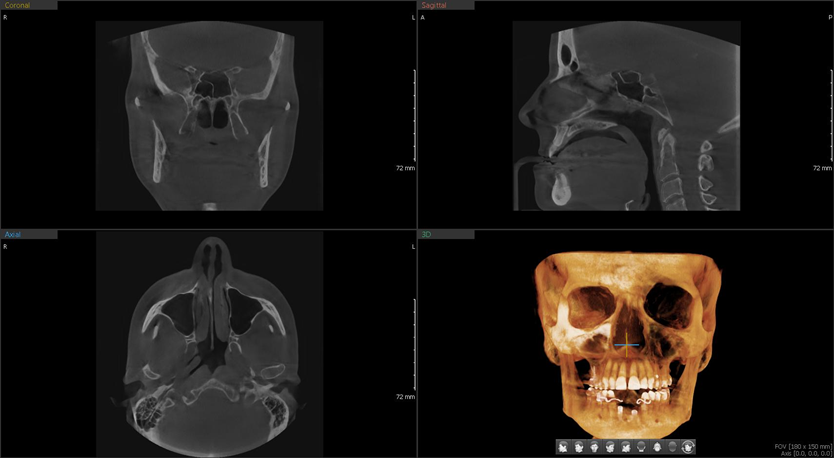

GRAN FOV DE ESCANEO

Green X tiene una amplia gama de campos de visión para que puedas elegir FOV óptimo minimizando la exposición en áreas que no están en la región de interés.

La selección de FOV se adapta a tus necesidades de diagnóstico: 16×15 (opcional), 16×9, 12×9, 8×9, 8×5, 5×5 y 4×4. Estas opciones abarcan toda la región del arco, seno y ATM (izquierda /derecha) y se adapta a la mayoría de los casos de cirugía y cirugía de implantes múltiples.

Tomografía